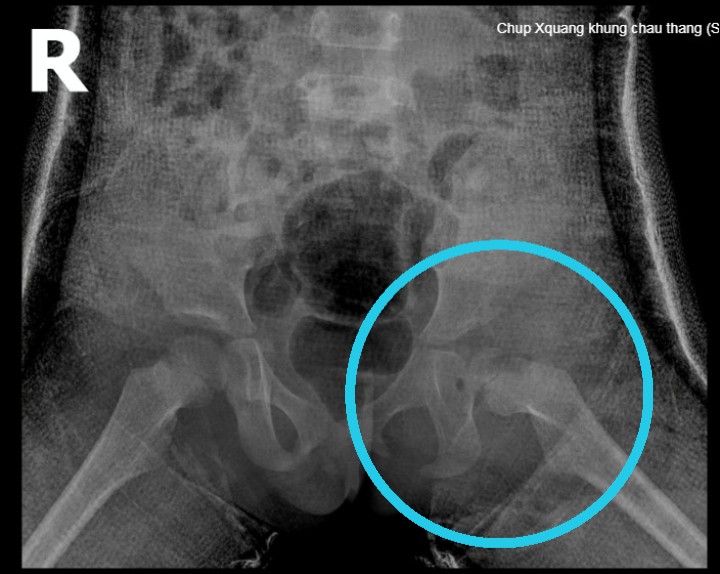

Tại đây các bác sĩ chẩn đoán cháu bị trật khớp háng bẩm sinh bên trái. Và có chỉ định phẫu thuật vì cháu đã lớn, không còn điều trị bảo tồn được nữa. Qua 3 giờ phẫu thuật, khớp háng của bệnh nhi được đưa về đúng giải phẫu, tuy nhiên cần được bó bột tăng cường thêm 6 đến 8 tuần, mới có thể tháo bột và tập đi trở lại.

Hình ảnh chụp X-quang cho thấy bệnh nhi trật khớp háng bẩm sinh bên trái